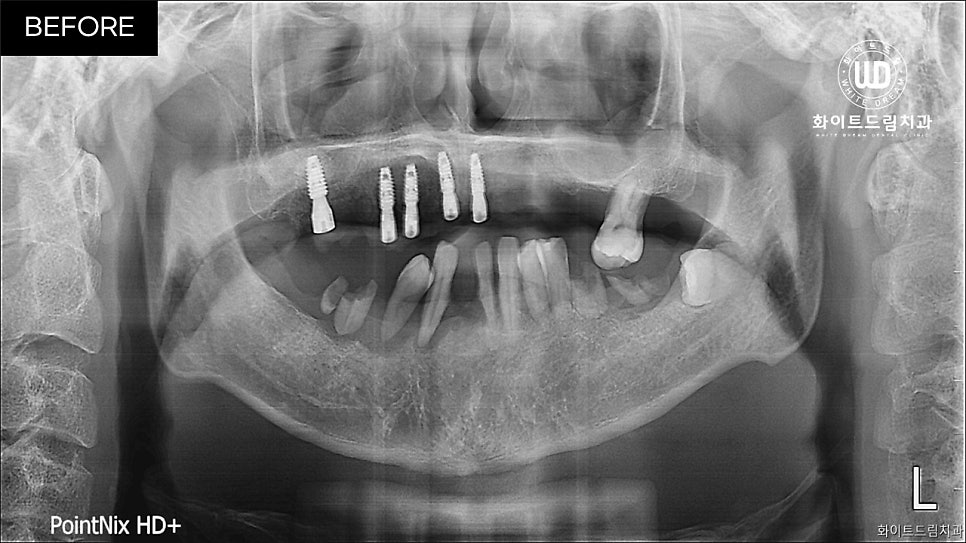

치아 발치 및 일부 픽스쳐가 식립된 모습입니다.

중간상태임을 감안하여도 픽스쳐가 고르게 식립된걸 확인할 수 있습니다.

임플란트 식립 전 뿌리조각이 남아있다면 뼈와 붙는 현상에 방해가 될 수 있습니다. 그렇기 때문에 임플란트 나사부분과 뼈가 단단하게 붙을 수 있도록 꼼꼼하게 전체 발치 후, 소량의 나사를 우선 식립 해드렸는데요.